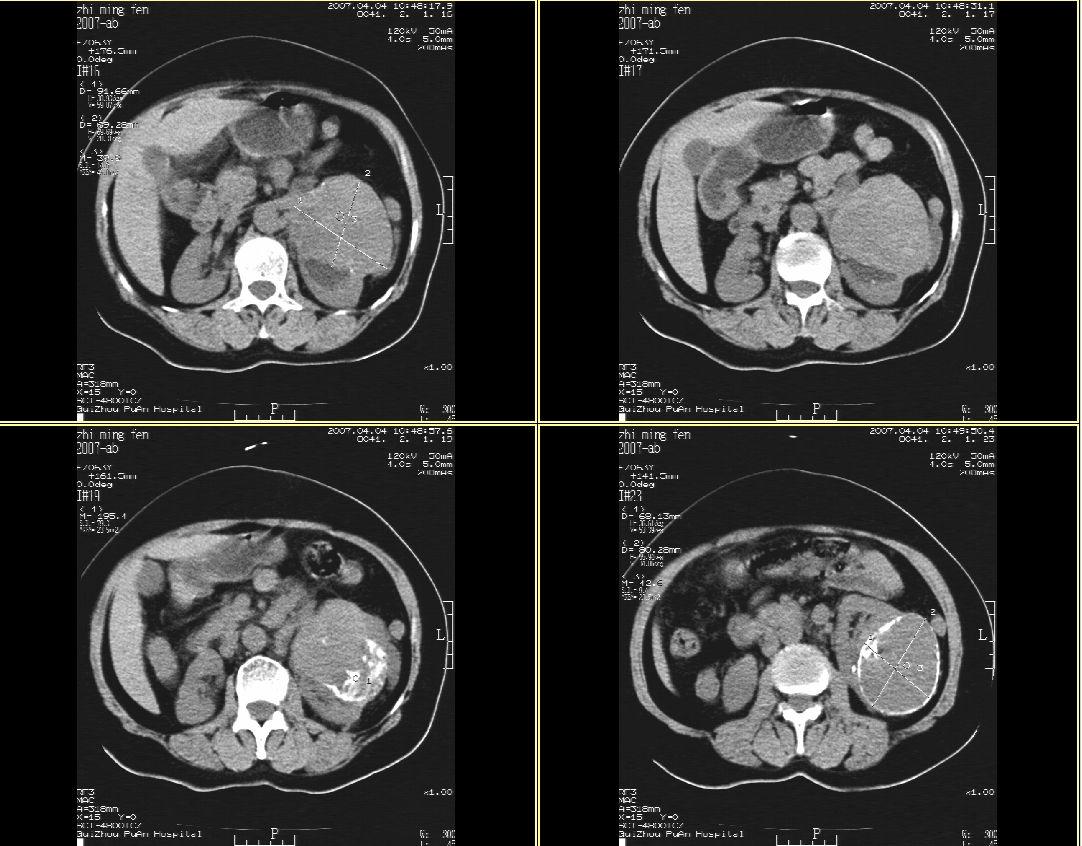

以下是引用hhcckk在2007-4-9 9:18:00的发言:[br]我认为就是一个病灶,病灶上端密度较均匀,下方有明显的钙化,部分呈不完全的环状,考虑肾癌[br]1、肾癌的特征性ct表现为肾实质的占位,局部隆起外突[br]2、肿瘤内的钙化常见,多发生在肿瘤内部,也可以在肿瘤周边呈弧型或不完全的环行钙化[br]3、最常见的三大症状,血尿,腰痛,包块此病人也较符合,增强吧

以下是引用swyyy2007在2007-4-9 18:42:00的发言:[br]支持左肾癌累及肾窦肾盂,左肾积水 [br] [br]